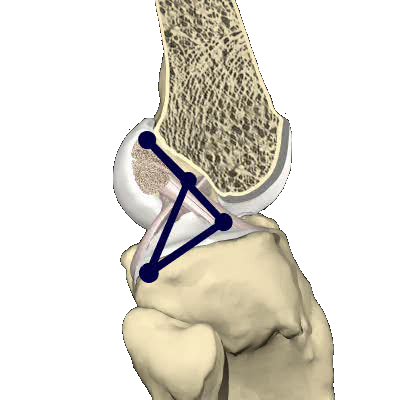

Please annotate this diagram with the site(s) of swelling or tenderness.

Right Knee

Notes: -

Left Knee

Notes:-

Is there detectable instability: Yes / No

This is notoriously difficult to assess immediately after injury as pain inhibition limits the passive envelope of movement of the knee.

Notes:-